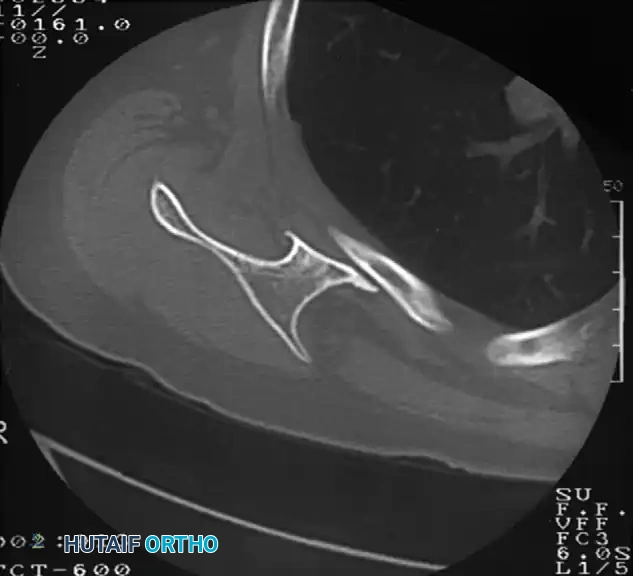

Snapping Scapula Syndrome (Scapulothoracic Crepitus)

Though not explicitly detailed in the raw extract, snapping scapula is a critical component of shoulder snapping syndromes. It is caused by the disruption of the smooth gliding motion between the anterior scapula and the posterior thoracic cage.

Pathologies include osteochondromas of the ventral scapula, Luschka's tubercle enlargement, or fibrotic bursitis (scapulothoracic bursitis). Advanced imaging, particularly CT scans with 3D reconstruction, is invaluable for identifying ventral scapular exostoses. Refractory cases are treated with arthroscopic or open partial scapulectomy (resection of the superomedial angle) and bursectomy, yielding high rates of symptomatic relief and restoration of normal shoulder kinematics.